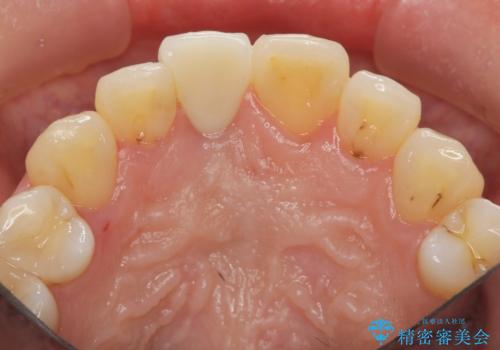

- 幼少期に前歯をぶつけて歯が折れ、神経の治療・クラウン治療を行った。グラつきと見た目の改善を希望して来院されました。

精密な仮歯をいれ、歯周組織を整えるとともにファイバーコア築盛、シェードテイキングを行い見た目に自然なジルコニアクラウンを製作していきます。

ジルコニアクラウンの中でも当法人のグレードの高い、スペシャル・エクセレントプランはオーダーメイドで色調を合わせることで周囲の歯に馴染んだ自然な歯を製作することのできるプランです。